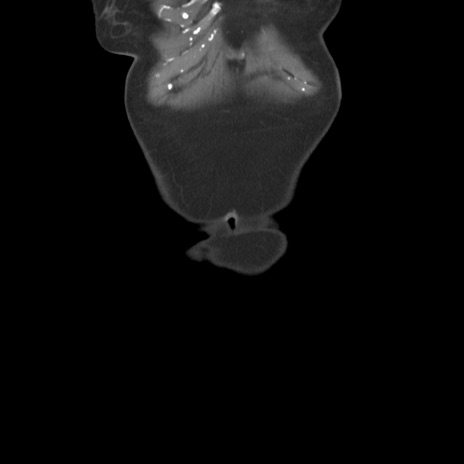

症例19(冠状断像)

【症例】80歳代女性

【主訴】下腹部痛

【現病歴】約8時間前より下腹部痛の出現あり、救急外来受診。

【既往歴】両側付属器切除

【身体所見】意識清明、下腹部正中に手術痕あり、その部位に一致して圧痛と反跳痛あり。腸蠕動音は亢進。

【データ】WBC 9300、CRP 0.15